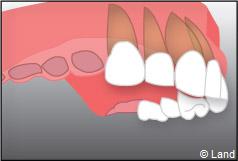

– le remplacement d’une dent unitaire. Grâce à ce procédé, il n’y a pas de mutilation des dents voisines.

– le remplacement de plusieurs dents manquantes par un bridge sur implants. Cela évite l’appareil amovible.

Le choix se fait en fonction de l’emplacement, de la quantité d’os disponible, et des éléments anatomiques environnants à partir d’examens cliniques, radiologiques et scanner de la zone à implanter.